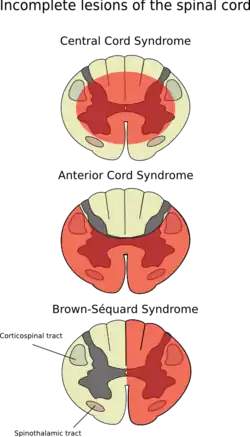

Brown-Séquard syndrome (also known as Brown-Séquard's hemiplegia, Brown-Séquard's paralysis, hemiparaplegic syndrome, hemiplegia et hemiparaplegia spinalis, or spinal hemiparaplegia) is a neurological condition caused by damage to one half of the spinal cord. The condition presents clinically with spastic paralysis and loss of fine touch perception, vibratory sensation and proprioception just below the lesion on the same side of the body as the lesion, but with loss of crude touch, pain an temperature sensation and on the opposite side and beginning somewhat lower than the lesion. At the level of the lesion, on the same side of the lesion, there is meanwhile a region of flaccid paralysis and complete loss of all sensation.

The syndrome is frequently encountered in clinical practice, but only rarely presents in its classical form[2] because most lesions are irregular;[3] partial hemisection is common, but complete hemisection is rare.[4] The development of characteristic pathology is preceded by a period of spinal shock.[5]

The hemisection of the spinal cord produces the classical triad characterising this syndrome by disrupting the following three structures of the spinal cord: